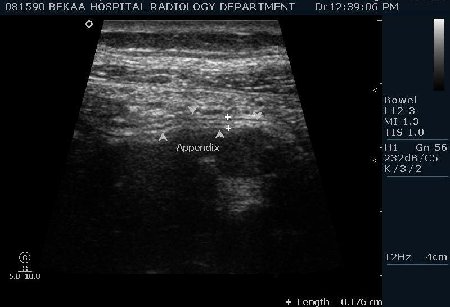

Диагностика острого аппендицита по УЗИ: очень актуальная тема; УЗ аппараты практически есть во всех клиниках; метод доступный и не сложный; главное владеть правильной техникой. Не буду загружать лишней теорией и разными ссылками; поделюсь практическим опытом. У меня линейный датчик 3-12 мегагерц с плавающей частотой; аппарат Филипс HD 11, всегда включаю соно-КТ (9800 цифровых каналов) и гармонику когда смотрю кишечник. Нормальный аппендикс видеть можно; но вопрос зачем??? Как правило, если при наличии достаточного опыта аппендикс не виден; значит скорей всего аппендицита нет. Когда "идешь" на аппендицит то главное по началу набраться терпения и......хорошая компрессия! По началу надо минут 10-15; потом когда появится достаточный опыт; за 2-5 минут можно справится и получить отличную визуализацию. Мочевой пузырь лучше опорожнить; часто он приподнимают тонкий кишечник и может закрыть "окно" через которое будет видно апендикс. Сначала находим слепую кишку потом находим илео-цекальное соединение;

после начинаем производить хорошую компрессию датчиком попрося пациента сообщить в какой точке боль наиболее выражена; медленными движениями датчика сканируем область наибольших болевых ощущений и как правило находим утолщенный отросток. Лучше начинать с поперечной визуализации и идти к верхушке аппендикса что бы убедится что это аппендикс и он заканчивается, а не тонкая кишка (которая если и закончится то только переходя в слепую); потом надо аккуратно развернуть продольно датчик и посмотреть от верхушки аппендикса к слепой. Норма диаметра: 3-4 мм; 5-6 мм под вопросом (клиника решает; но я в катаральный аппендицит не верю); 7-8 мм и больше, не компремируемый (фиксированный отросток)-острый аппендицит! Помимо наличие утолщенного аппендикса; признака "бычьего глаза" (bull-eye sign) при поперечном сканировании; надо обращать внимание на присуствие аппендоколитов в просвете; деструкцию стенки и свободной жидкости в зоне интереса.